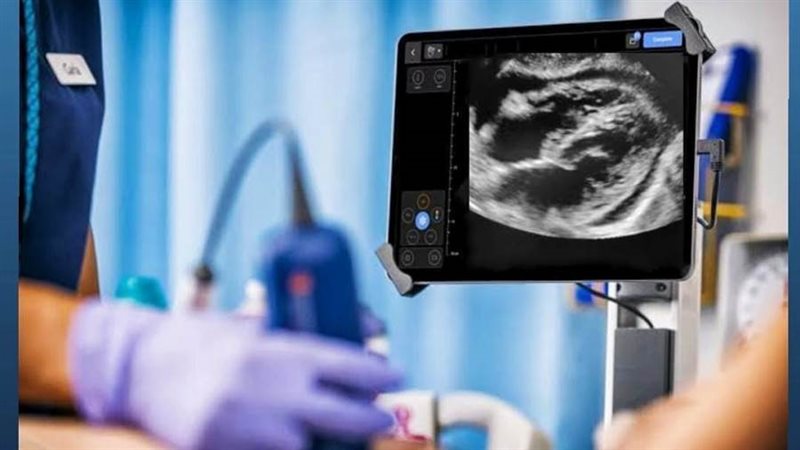

طبقًا لتوجيهات "ا.د.مها ابراهيم"، رئيس أمانة المراكز الطبية المتخصصة، التركيز على تقديم خدمات طبية طارئة ومتميزة لجميع المرضى، ومتابعة وإشراف د.ميرفت السيد"، مدير المركز الأفريقى لخدمات صحة المرأة والمشرف العام على مستشفيات أمانة المراكز الطبية المتخصصة بالإسكندرية، تم إعلان نجاح فريق قسم الطوارئ بالتعاون مع فريق قسم عناية القلب في مستشفى شرق المدينة بقيادة "د.عبد الله الفرماوي"، مدير المستشفى، من إنقاذ حياة مريضة شابة تبلغ من العمر 34 عامًا، حيث حضرت إلى قسم الطوارئ بمستشفي شرق المدينة، وهي تعاني من ضيق شديد في التنفس وهبوط شديد بضغط الدم، وقام فريق الطوارئ بعمل التقيييم الطبي والفحوصات اللازمة وقام الأطباء بالطوارئ باستخدام جهاز السونار (Point of Care Ultrasound) بتشخيص حالتها، والتي أظهرت وجود تجمع كبير من السوائل حول القلب مما تسبب فى ارتشاح كبير حول القلب، أدى إلى انضغاط واختناق القلب، (Cardiac Tamponade) موضحة أنه إذا لم يتم التدخل الجراحي السريع يحدث توقف لعضلة القلب، الحالة التي تتطلب تدخلاً عاجلاً لإنقاذ الحياة.

واضافت "د.ميرفت السيد" أن الفريق الطبي بقسم الطوارئ برئاسة د. ريهام كارم محمد، أخصائي الطوارئ و د. بولا سمير أخصائي القلب، قد قاما بإجراء تدخل طارئ لسحب السوائل حول القلب باستخدام التوجيه بالموجات فوق الصوتية (Ultrasound-Guided Pericardiocentesis)، حيث تم تصريف حوالي 1.5 لتر من السائل النزفي.